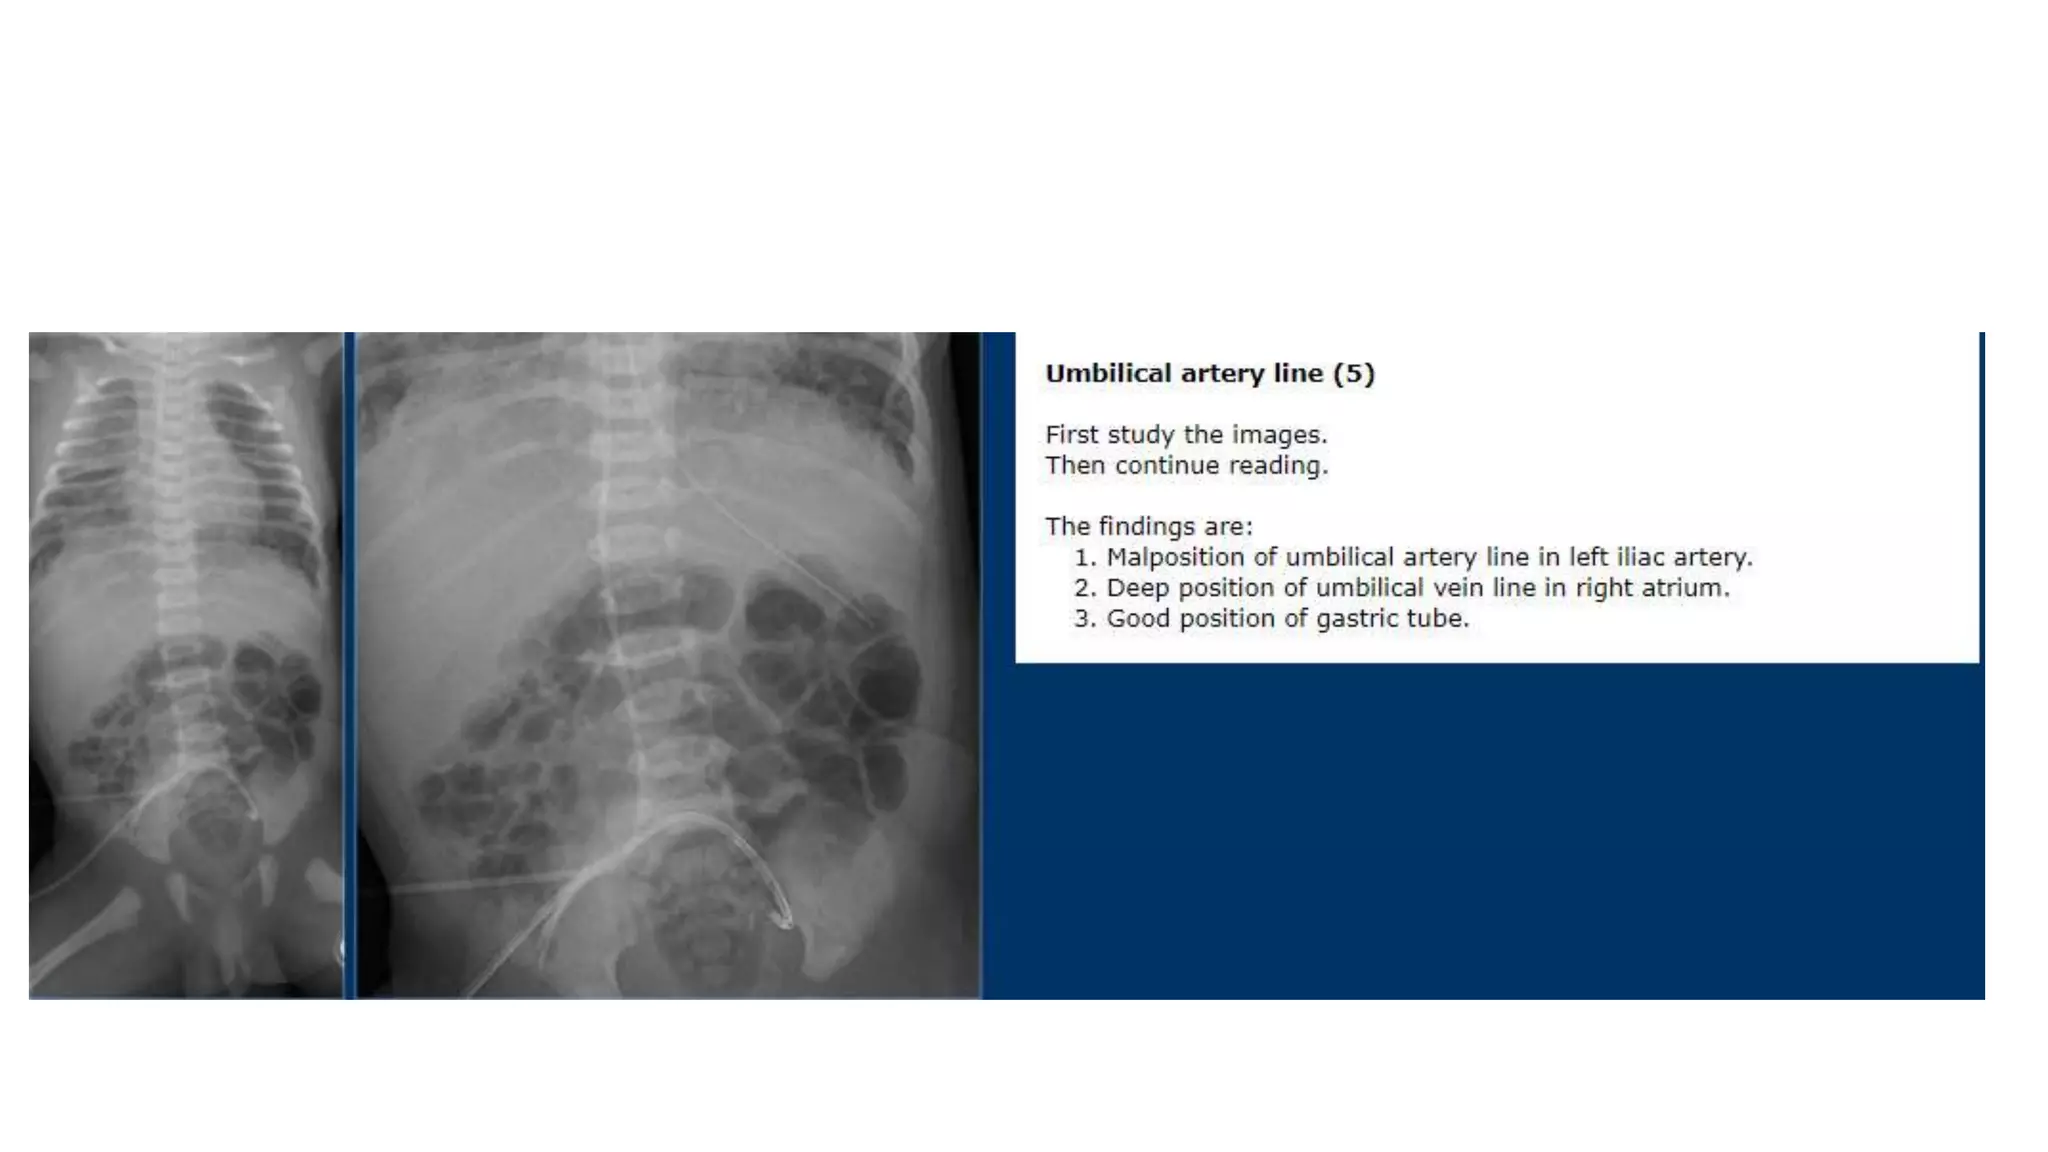

This document provides an overview of neonatal chest x-rays, including when they should and should not be performed, what a normal x-ray looks like, common positions of tubes and catheters, and common causes of respiratory distress in neonates. It discusses the appearance of a normal chest x-ray as well as conditions like respiratory distress syndrome, transient tachypnea of the newborn, meconium aspiration syndrome, and pneumonia. Surgical conditions like diaphragmatic hernia and esophageal atresia are also reviewed.